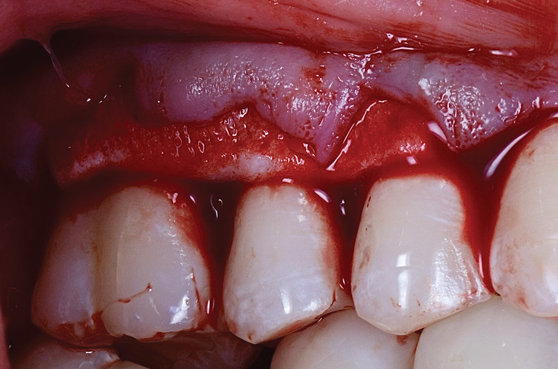

Vestibular approaches (eg, vestibular incision subperiosteal tunnel access)17 are variations on tunnel flaps that address many of the challenges presented by the basic design (Figure 3). By making an incision in the vestibule, instruments may be passed beneath the mucoperiosteum to create space and passivity of the flap while minimizing the chances of creating perforations or tears in critical areas, such as the facial gingival margin. Depending on the size of the vestibular incision, either a sulcular access or vestibular access can be used for placement of the graft material. Unfortunately, because vestibular approaches are essentially still tunnel flaps, lack of root access remains an issue.

(3.) Example of the vestibular tunnel approach, which is a variation of the tunnel flap that addresses many of the challenges associated with tunnel flaps.

Figure 3